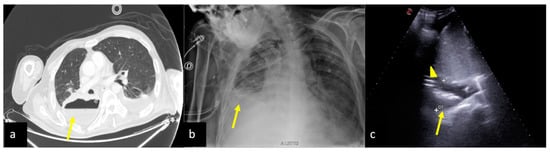

2.3. Pleural Effusion